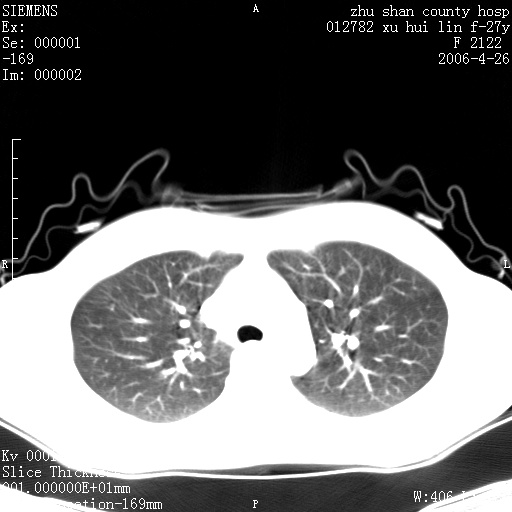

女性 病人 27岁!本院职工家属,五月前因感冒透视发现病变,ct示:左肺下叶背段感染性病变。经过半月规范抗生素治疗后复查病变无明显变化,后行四月规范抗痨治疗,复查无明显变化,后复查无效!请大家帮忙看看!

右肺下叶背段见片状高密度区,边界不清,密度不均,无钙化及空洞影,背段支气管通畅。所见层面肺门及纵隔内未见明显肿大淋巴结影。

诊断:首先还是考虑为慢性炎症。

结核虽然好发于下叶背段,但周围无明显卫星灶,化验结果怎样?